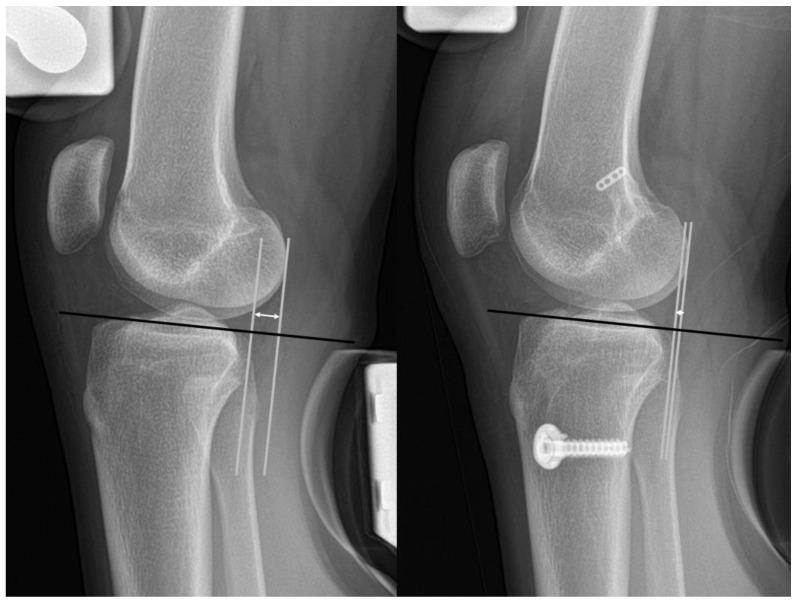

This study aims to identify potential factors for both femoral and tibial tunnel widening (TW) and to investigate the effect of TW on postoperative outcomes after anterior cruciate ligament (ACL) reconstruction with a tibialis anterior allograft. A total 75 patients (75 knees) who underwent ACL reconstruction with tibialis anterior allografts were investigated between February 2015 and October 2017. TW was calculated as the difference in tunnel widths between the immediate and 2-year postoperative measurements. The risk factors for TW, including demographic data, concomitant meniscal injury, hip-knee-ankle angle, tibial slope, femoral and tibial tunnel position (quadrant method), and length of both tunnels, were investigated. The patients were divided twice into two groups depending on whether the femoral or tibial TW was over or less than 3 mm. Pre- and 2-year follow-up outcomes, including the Lysholm score, International Knee Documentation Committee (IKDC) subjective score, and side-to-side difference (STSD) of anterior translation on stress radiographs, were compared between TW ≥ 3 mm and TW < 3 mm. The femoral tunnel position depth (shallow femoral tunnel position) was significantly correlated with femoral TW (adjusted = 0.134). The femoral TW ≥ 3 mm group showed greater STSD of anterior translation than the femoral TW < 3 mm group. The shallow position of the femoral tunnel was correlated with the femoral TW after ACL reconstruction using a tibialis anterior allograft. A femoral TW ≥ 3 mm showed inferior postoperative knee anterior stability.

本研究旨在确定股骨和胫骨隧道增宽(TW)的潜在因素,并探讨胫骨前肌自体移植重建前交叉韧带(ACL)后TW对术后结果的影响。2015年2月至2017年10月期间,共对75例行胫骨前肌自体移植ACL重建术的患者(75膝)进行了研究。TW计算为术后即刻与术后2年隧道宽度的差值。研究了TW的危险因素,包括人口统计学数据、合并半月板损伤、髋-膝-踝角、胫骨坡度、股骨和胫骨隧道位置(象限法)以及两条隧道的长度。根据股骨或胫骨TW是否超过或小于3 mm,将患者两次分为两组。比较了TW≥3 mm组和TW<3 mm组术前和术后2年的结果,包括Lysholm评分、国际膝关节文献委员会(IKDC)主观评分以及应力X线片上前移的侧方差异(STSD)。股骨隧道位置深度(股骨隧道浅位置)与股骨TW显著相关(校正后=0.134)。股骨TW≥3 mm组的前移位STSD大于股骨TW<3 mm组。胫骨前肌自体移植重建ACL后,股骨隧道浅位置与股骨TW相关。股骨TW≥3 mm显示术后膝关节前稳定性较差。